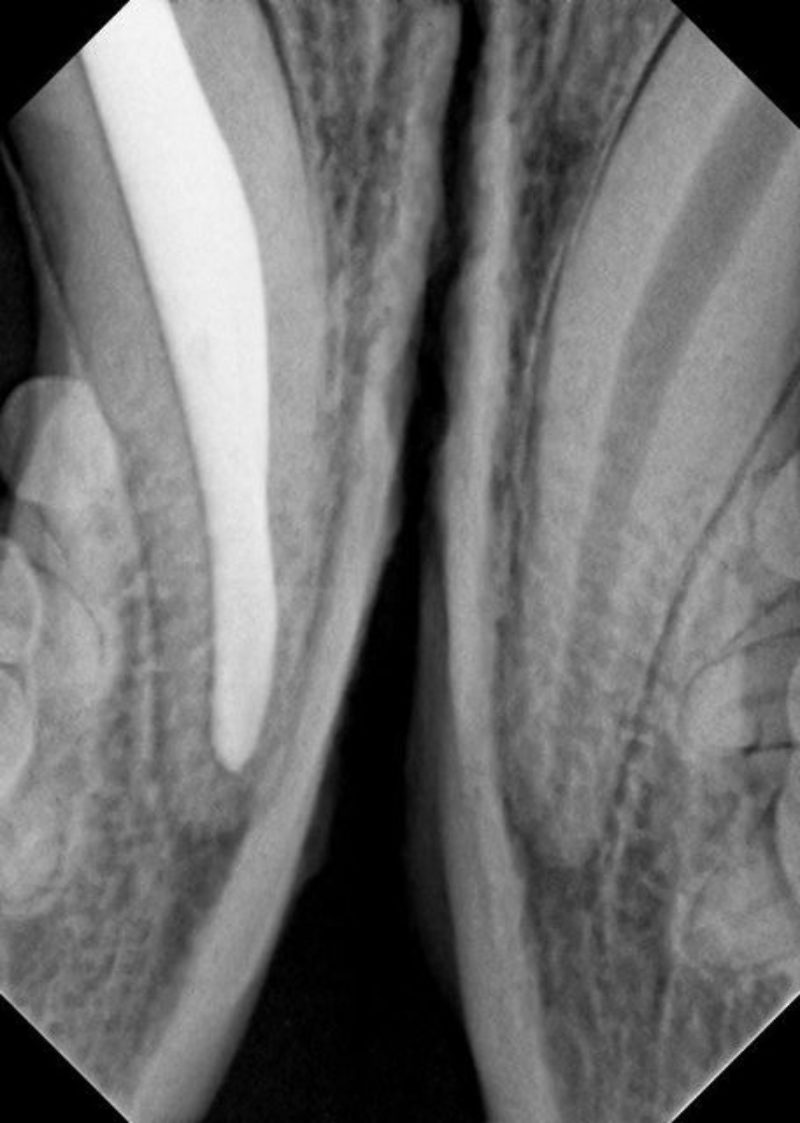

Zuerst wurde die Pulpenhöhle über einen Hilfszugang von vorne eröffnet, um einen  möglichst gradlinigen Zugang zur Wurzelspitze zu erhalten. Dann wurde die eitrig entzündete Pulpa entfernt. Unter Spülung mit desinfizierenden Lösungen wurde die Pulpenhöhle mit dünnen Feilen in aufsteigender Größe gereinigt und ausgeformt. Nach Entfernung der sogenannten Schmierschicht wurde der Pulpenkanal mit Kochsalzlösung gespült und mit feinen Papierspitzen getrocknet. Es schloss sich die Einpassung des sogenannten Master-Points an, eines dünnen Kautschuk-Stiftes aus Guttapercha, der die Wurzelspitze verschließen soll. Hierzu wurde eine kleine Menge  Sealer in die Pulpenhöhle eingebracht, ein Material, das die kleinsten Kanäle im Bereich der Wurzelspitze abdichtet und in Verbindung mit dem Masterpoint den hermetischen Verschluß der Pulpenhöhle Richtung Wurzelspitze übernimmt. Nach dem Einbringen und Verdichten weiterer kleinerer Guttapercha-Stifte erfolgte eine Zwischenfüllung und schließlich eine Deckfüllung aus Kunststoff, um die Pulpenhöhle auch zur Zahnkrone hin abzudichten. Nach Ausarbeitung der Füllung und Politur konnte „Piko“ schließlich aus der Narkose aufwachen. „Piko“ konnte bereits am nächsten Tag wieder arbeiten.

Anders als bei uns Menschen können Wurzelbehandlungen beim Tier in vielen Fällen in nur einer Behandlungssitzung abgeschlossen werden. Die Erfolgsprognose einer Wurzelkanalbehandlung ist mit über 85% sehr hoch, was auch den Aufwand der Behandlung rechtfertigt.